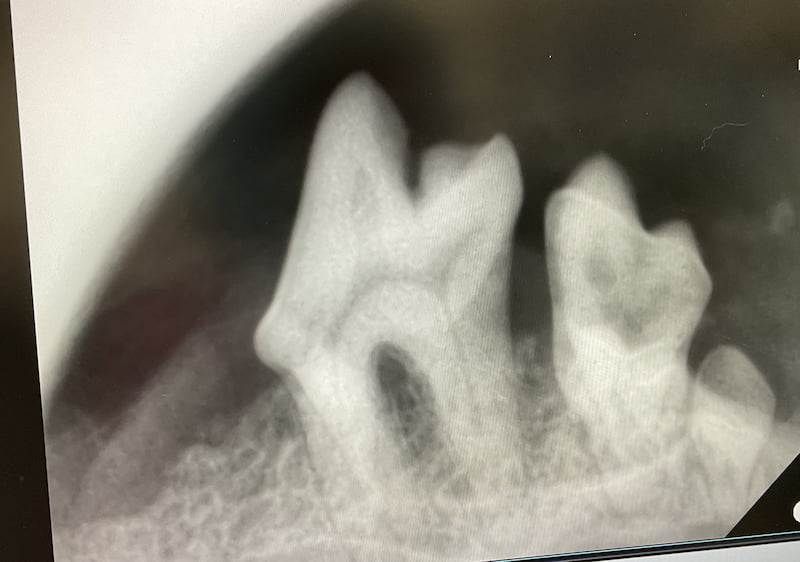

外から見えない歯肉の中で起きている病気などを特定するために行われる検査です。歯科用プローブを使い、歯周ポケットの状態を調べたり、歯周病菌が産生する特殊な物質を検出するテスターを用いて検査することができます。 - 口腔内レントゲン検査

歯、顎骨、鼻腔内の検査に用います。口腔内レントゲン検査に関しては、通常のレントゲンでは検査できない部位の撮影が可能です。